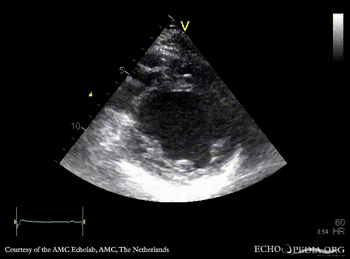

E00707.gif E00708.gif

A4CH: dilated left ventricle, poor function, akinesia of inferoseptal wall A2CH: dilated left ventricle, poor function, akinesia of inferior wall